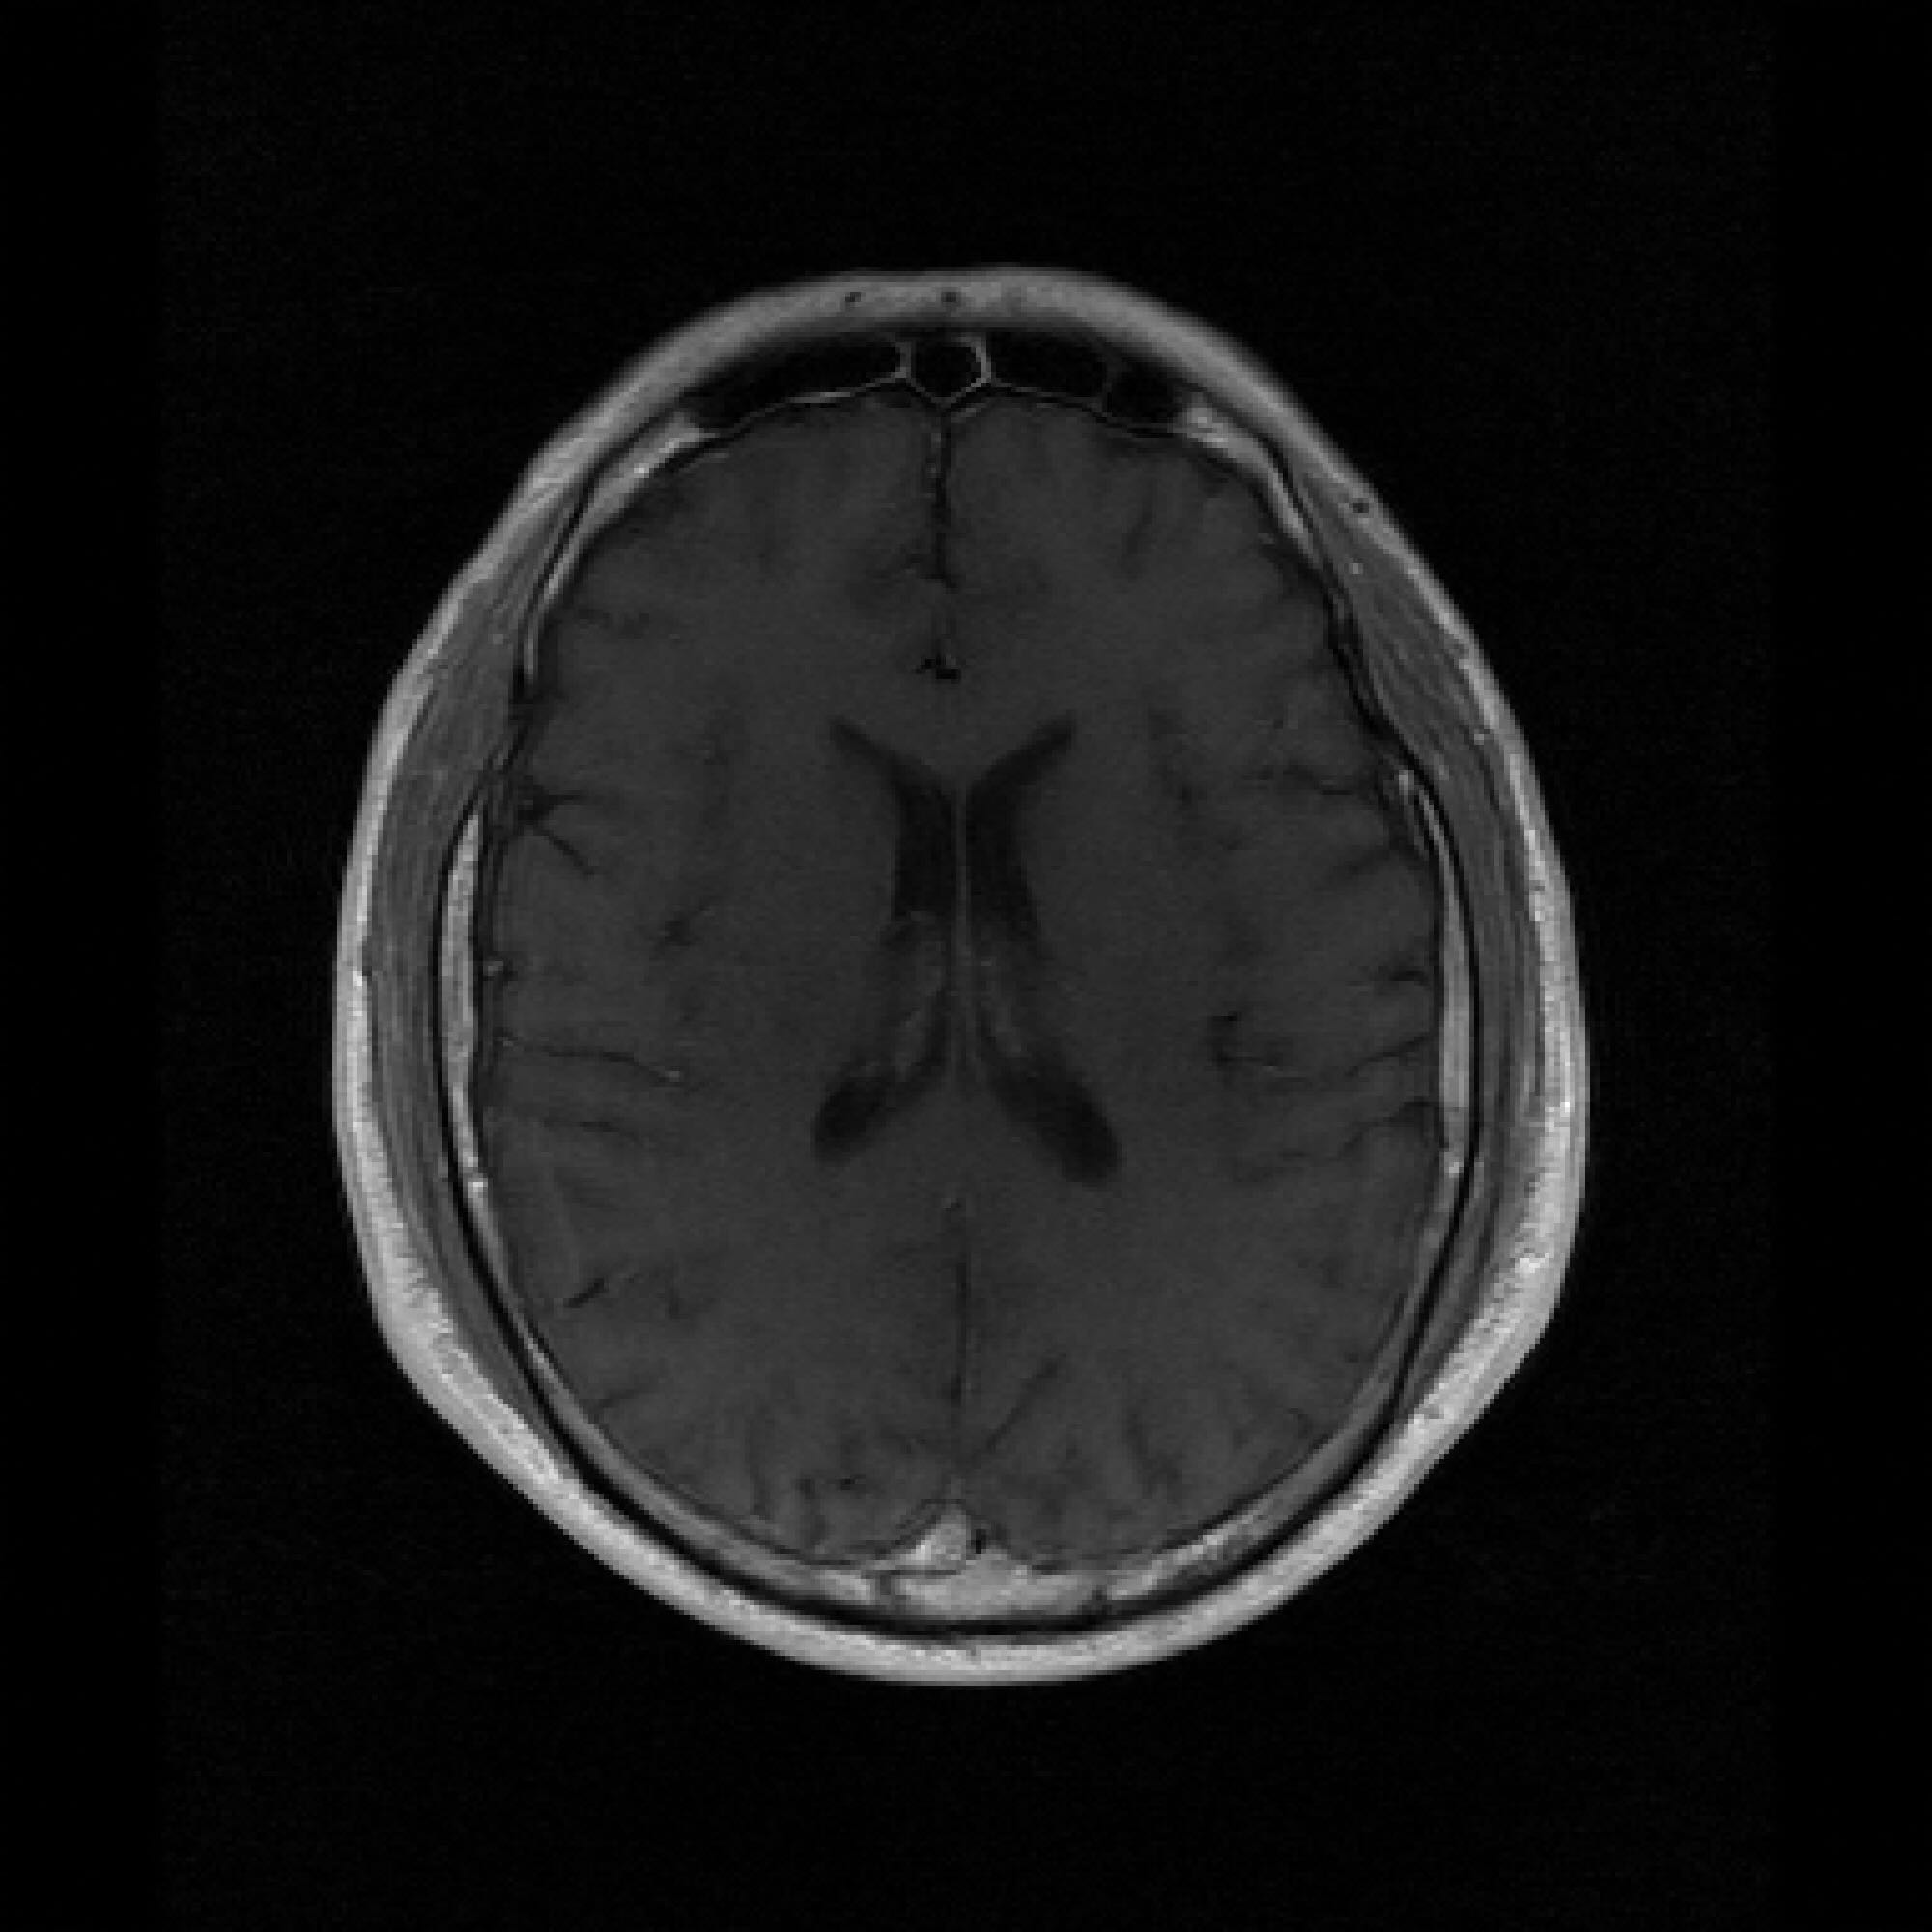

B.3 Unconditional Generation Quality

Figure 5 shows sampled unconditional generations for both PaDIS-MRI and FastMRI-EDM, at model convergence. As discussed previously, we trained models by qualitatively evaluating the change in unconditional generation quality over time. The FastMRI-EDM model is able to capture more detailed anatomy in its unconditional generations, whereas PaDIS-MRI tends to generate more uniformly gray ovals with limited detail. We hypothesize that the relatively poorer-looking unconditional generations of PaDIS-MRI may actually make it more robust during inference, or conditional generation. Rather than capturing intricate global features, the relatively simple structure may provide a form of implicit regularization that favors locally consistent features over potentially spurious or overfitted global patterns.

Figure 5: Unconditional image generation quality comparison between FastMRI-EDM (top row) and PaDIS-MRI (bottom row) across different training dataset sizes (25 to 2330 slices, indicated above each column). PaDIS-MRI produces less visually intricate unconditional generations, yet provides a more reliable prior for conditional generation in undersampled MRI reconstruction.